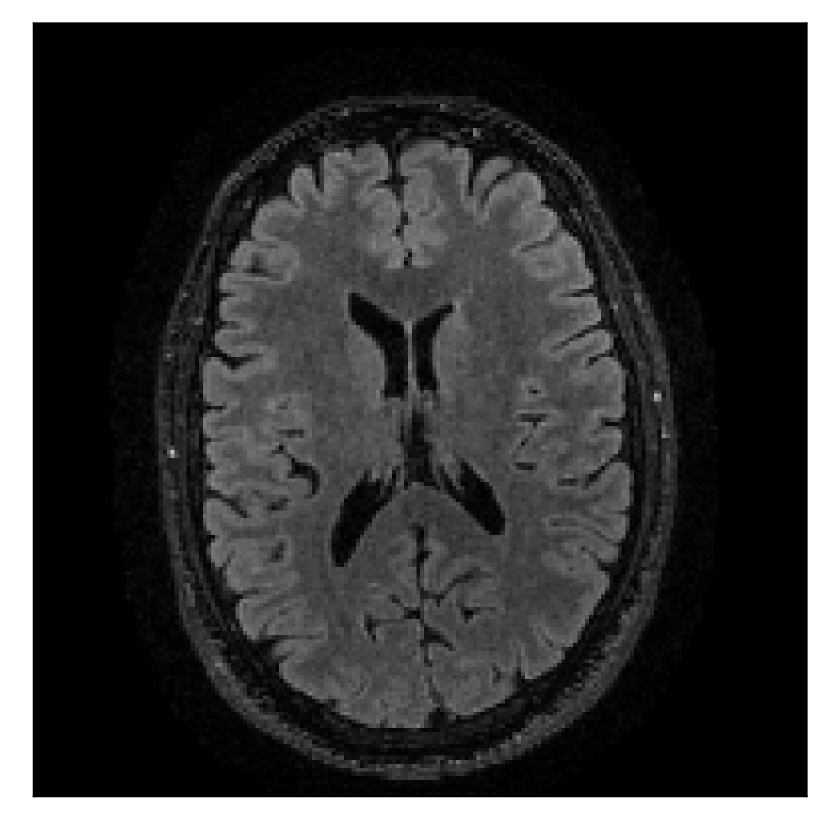

| Section 3.2, Figure 10 | Sagittal | 25.84 | 28.07 | 0.7032 | 0.8093 |

| Coronal | 26.35 | 30.40 | 0.7851 | 0.9021 | |

| Axial | 28.11 | 30.54 | 0.8248 | 0.9012 | |

The motion-corrected full-volume scans were analyzed by a neuroradiologist with 16 years of experience. These were generally deemed of good radiological quality. The motion-related artifacts have been completely removed, and the results are quite close to the ground truth. In Table 3, we organized a more detailed qualitative analysis of the 3D results, geared toward a radiological assessment of the corrected scans.

| Experiment | Contrast | Motion resolution | Blurring | Artifacts | Additional comments |

| Section 3.2, Figure 10 | T1 | Completely corrected | Some blurring | No additional artifacts | Good grey white matter differentiation, |

| some loss of grey matter low signal | |||||

4.2 Experiment 2: choice of the reference contrast

With the experiment described in Section 3.2, we demonstrate the flexibility of the correction scheme with respect to the choice of the reference contrast. The results are shown in Figure 10. Contrary to the experiments detailed in the previous section, we are now considering a T2-weighted reference contrast to guide the correction of a T1-weighted corrupted contrast. The quality of the correction indicates that the proposed technique is rather flexible in terms of reference contrast.

Furthermore, the flexibility of the proposed motion-correction method is demonstrated with different combinations of motion-corrupted and reference contrasts (Section 4.2). Our experience suggests that an important factor in assessing the effectiveness of the reference contrast as a guide for motion correction lies in the similarity of the -space distribution of the two contrasts. Good reconstruction quality can be expected when the reference contrast has similar or higher frequency content when compared to the corrupted contrast, regardless of the type of contrast considered.